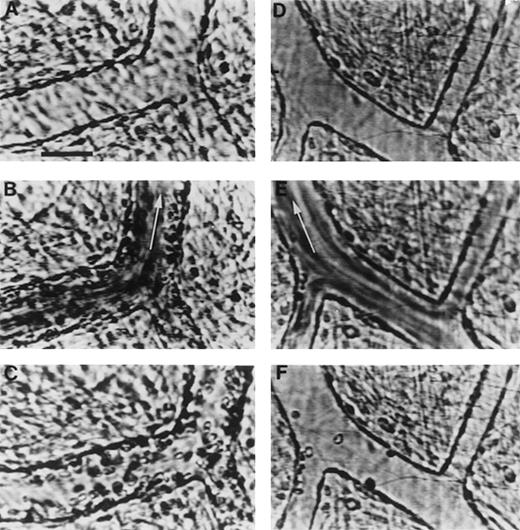

Videomicrographs showing inhibition of PAF-induced SS RBC adhesion in the ex vivo mesocecum vasculature in the presence of MoAb 7E3 F(ab′)2.

(A-C) Ex vivo preparation treated with OC125 F(ab′)2(control antibody) and PAF: (A) clear venular lumen during artificial perfusion with Ringer-albumin; (B) the passage of SS RBCs after a bolus infusion is accompanied by adhesion of these cells in venules; (C) after the passage of the bolus, a large number of SS RBC are seen adhering to the vessel wall during perfusion with Ringer-albumin. (D-F) Ex vivo preparation treated with MoAb 7E3 and PAF: (D) venules during the artificial perfusion; (E) rapid flow of SS RBCs in the vessels after a bolus infusion; (F) after the passage of the bolus, only few SS RBC adhere to the vessel wall. Visit the article on the website (www.bloodjournal.org) to download the video.

In preparations pretreated with the control antibody and PAF, there was pronounced adhesion of SS RBC to the venular endothelium (Figure 3A and C). In marked contrast, in preparations pretreated with 7E3 F(ab′)2, there was minimal SS RBC adhesion in four experiments and moderate SS RBC adhesion in one experiment (Figure 3D and F). Quantitative analysis of the number of adherent SS RBCs per 100 μm2 as a function of venular diameter revealed marked inhibition of SS RBC adhesion by 7E3 F(ab′)2 even in the smaller-diameter venules, the sites of maximal adhesion. As a result, the Y-intercept of the data plotted in Figure 6 was markedly different for the preparations treated with the control F(ab′)2 (0.55 SS RBC/100 μm2) and the 7E3 F(ab′)2(0.02 SS RBC/100 μm2; P < .0001). The slopes were also significantly different (P < .00001) because the 7E3 F(ab′)2–treated preparations did not demonstrate an inverse relationship between SS RBC adhesion and venular diameter. Furthermore, no obstruction of small-diameter postcapillary venules was evident in the presence of 7E3.